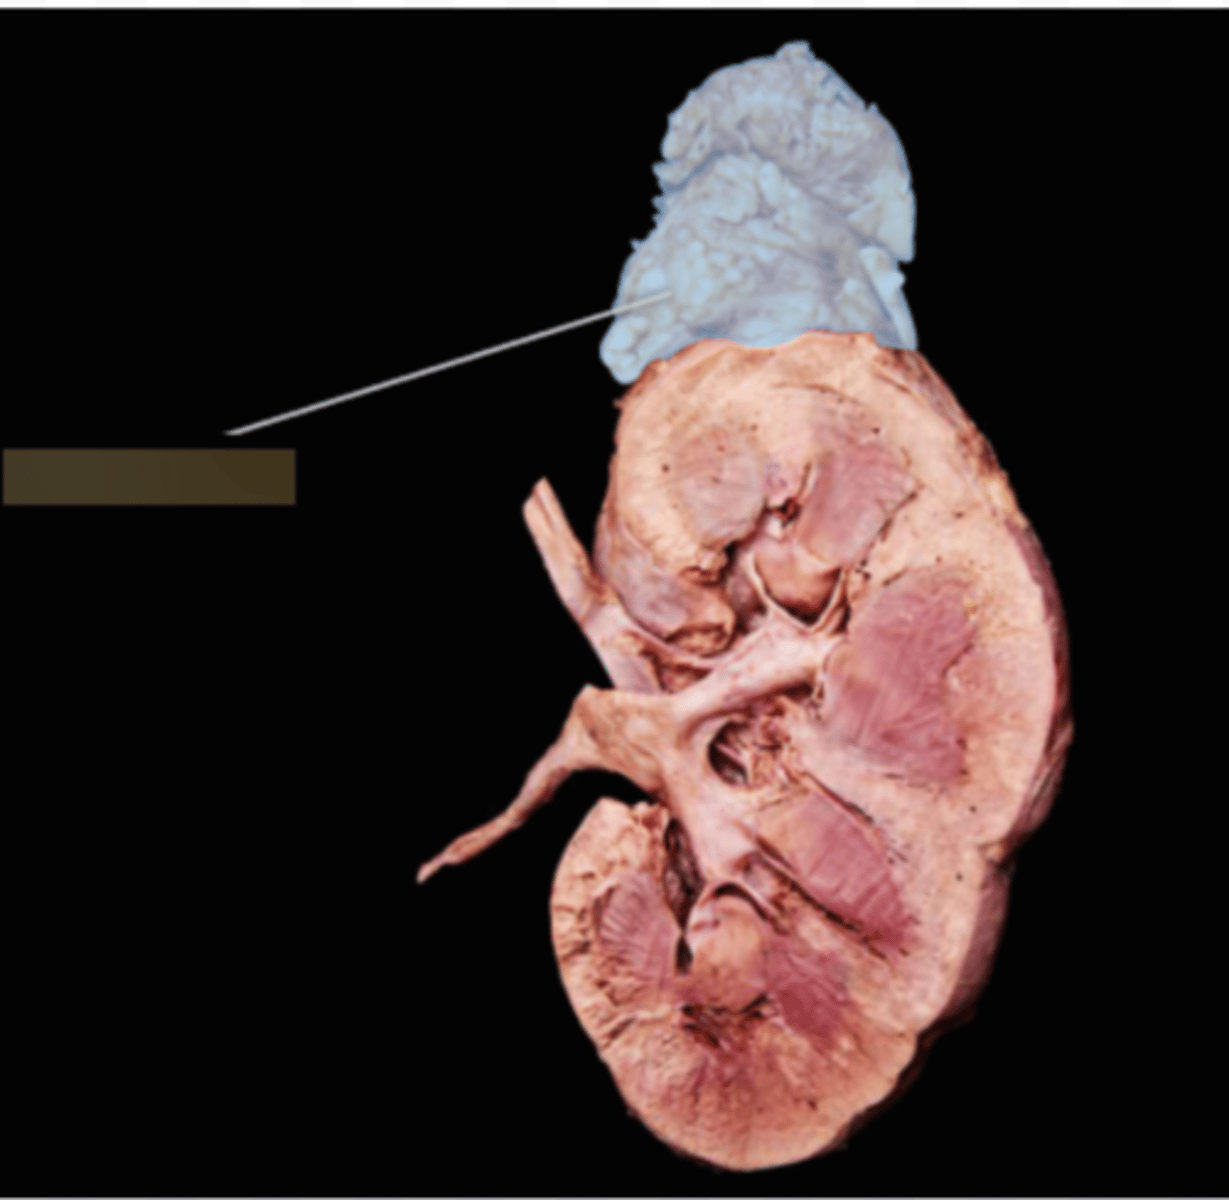

Right Kidney

Left Kidney

Renal Capsule

Renal Cortex

Renal Medulla

Papilla

Renal Column

Minor Calyx

Major Calyx

Renal Pelvis

Renal Hilum

Right Ureter

Left Ureter